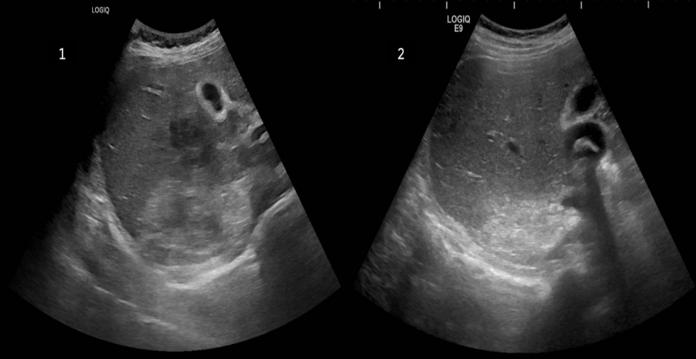

Figura 1. Diagrama de flujo de la muestra del estudio

una muestra de 396 individuos con el código CIAP K77 de IC en HCE de los 49.500 pacientes del centro de salud. La prevalencia de IC en este centro de salud fue del 0,8% (IC 95%:0,72-0,88).Deestamuestrainicial,seexcluyeron73 sujetos por no cumplir con los criterios diagnóscos para IC, no haber tenido citas en AP en el úlmo año o no encontrarseenelsistema(figura1)